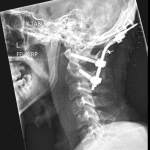

- Multiple tiny acute displaced fractures along the anterior aspects of both C1 superior articular facets with mild anterior subluxation of the occipital condyles relative to C1 and widening of the posterior aspect of both atlanto-occipital joints

- Widening of the C1-C2 interspinous interval and of the superior aspect of the sagittal atlantodental interval

- Fracture-subluxation at the craniocervical junction

Acute fracture-subluxation at the craniocervical junction with multiple tiny acute displaced fractures along the anterior aspects of both C1 superior articular facets, mild anterior subluxation of the occipital condyles relative to C1, widening of the posterior aspect of both atlanto-occipital joints, widening of the C1-C2 interspinous interval, and widening of the superior aspect of the sagittal atlantodental interval. MRI could further evaluate the extent of ligamentous injury.